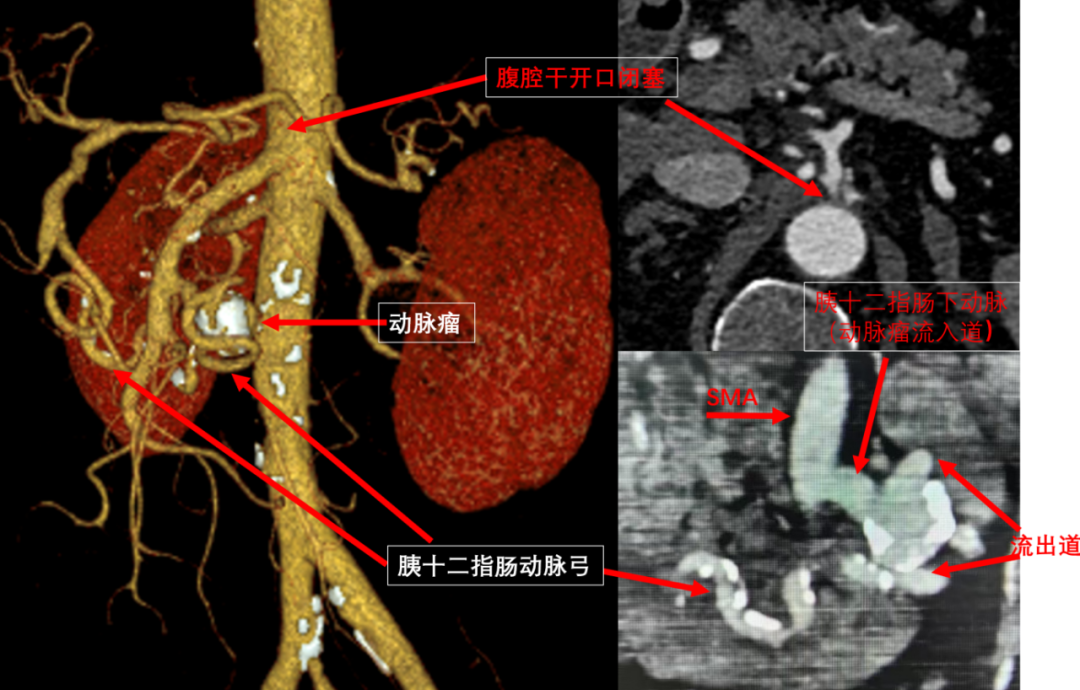

据悉,胰十二指肠动脉瘤,仅占内脏动脉瘤的2%,临床罕见,却是内脏动脉瘤中破裂风险最高的,其破裂与动脉瘤大小并无关联,一旦破裂死亡率达50%到80%。因此,胰十二指肠动脉瘤一经诊断,无论大小,均需尽快手术治疗。目前,治疗方案首选腔内介入治疗,用弹簧圈栓塞动脉瘤,而本例患者腹腔干闭塞,肝、脾、胰腺等脏器均靠胰十二指肠动脉弓供血,开展动脉瘤切除后,原位重建胰十二指肠动脉弓,患者术后恢复良好,顺利出院,无并发症发生。(青岛日报/观海新闻记者 黄飞)

山东大学齐鲁医院(青岛)普通外科血管外科专业将该患者收入院后,拟行腔内介入治疗,术中造影发现患者动脉严重迂曲,无法放置支架。若开展动脉瘤栓塞,可造成肝、脾、胰、胃肠等缺血坏死,于是改为开放手术。该手术由苏庆波、李峰主任医师主刀,术中发现,动脉瘤位于胰腺钩突系膜内,周围侧枝循环丰富,且与十二指肠水平段粘连紧密。医疗团队将其与胰腺、十二指肠游离后完整切除动脉瘤,并在原位重建胰十二指肠动脉。